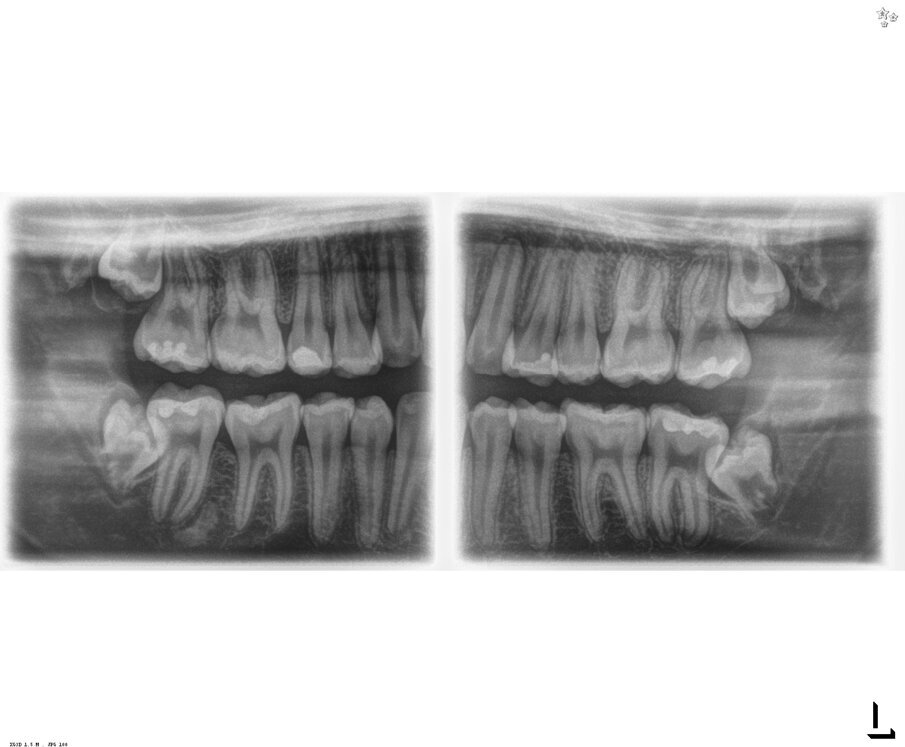

Si è presentata alla nostra osservazione la paziente A.M di 18 anni ASA 1 con disodontiasi di 38 e 48 lamentando fastidi localizzati all’area degli ottavi inferiori in fase finale di terapia ortodontica con allineatori trasparenti. Dall’ortopantomografia si poteva definire la classificazione di Pell e Gregory in classe II C e normoverso per quella di Winter (Fig 1). Vista la prossimità con il nervo alveolare inferiore, la incompleta formazione degli apici radicolari e la sintomatologia si è deciso insieme alla paziente di eseguire l’estrazione per ridurre i possibili rischi di danno neurologico dopo sottoscrizione del consenso informato. Previa anestesia tronculare della terza branca del V paio di sinistra con Carbocaina senza v.c. e plessica con Articaina 4% con v.c. 1:100000 si è proceduto all’incisione intrasulculare di 37 con scarico disto vestibolare. Lo scollamento del lembo mucoperiosteo è stato ottenuto mediante inserto PR1 al fine ottenere i vantaggi biologici come descritti da von See (Fig. 2).